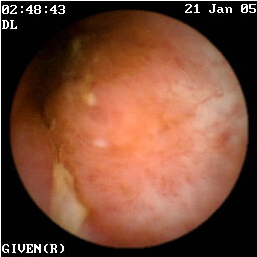

Mε βάση τις παραπάνω διεθνείς μελέτες7-13 αλλά και την εμπειρία της κλινικής μας σε 54 συνολικά ασθενείς με νόσο του Crohn, τα ευρήματα που παρατηρούνται στην εντεροσκόπηση με κάψουλα και συνηγορούν στη διάγνωση της νόσου είναι: α) οίδημα και ερυθρότητα του βλεννογόνου, β) οζώδης διαμόρφωση (εικόνες 3,4), γ) βλεννογονικές σχάσεις ή διαβρώσεις (εικόνα 5), δ) αφθώδη έλκη (ερυθηματώδης βλεννογόνος με μια λευκή κεντρική περιοχή) (εικόνες 6 -13), ε) γραμμοειδή, κυκλικά, ή ακανόνιστα έλκη (εικόνες 14-32) και στ) στενώσεις (εικόνες 33-35). Τα περισσότερα από τα παραπάνω ευρήματα παρατηρούνται στον ειλεό και ειδικά στο τελικό τμήμα του.

γαστρεντερολογος θεσσαλονικη  4

Εικόνες 3,4. Οίδημα και οζώδης διαμόρφωση του βλεννογόνου